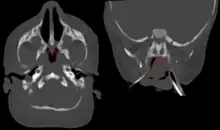

| Bilateral membranous choanal atresia in CT scan | |

Choanal atresia is diagnosed based on the inability to place a nasal catheter, and radiology results (particularly CT scans). Treatment involves maintaining an open airway, and may involve surgery to reopen the airway, potentially with a stent. Choanal atresia is a fairly rare condition, affecting between 1 in 7,000 to 1 in 5,000 live births. It is more common in females and is more often unilateral.

Diagnosis is confirmed using CT scan.[1][2] This is also useful for differential diagnosis.[1]